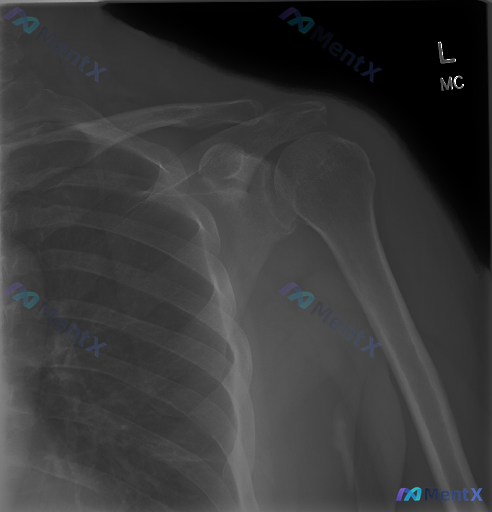

整理到一份左侧肩部的影像资料: - 只有正位X光片,报告写得很明确:左侧肩关节结构完整,对位好,没有骨折、脱位、骨赘、钙化斑块,也没有明显的退变或骨质破坏。 - 但同时有个提示说「存在异常」——意味着可能有临床症状或者其他预设信息,但影像上没直接看到。 大家遇到这种「影像阴性但临床高度怀疑有问题」的...

整理了一份左侧肩关节正位片的影像资料,报告结论很明确:未见明显骨性异常、急性外伤或严重退变。 但有意思的地方就在这里:如果拿到这份报告的患者,刚好有明显的肩痛、夜间痛、甚至外展无力,你第一眼会怎么考虑? 先放核心读片结果: - 骨骼:肱骨头、肩胛骨、锁骨远端完整,无骨折/脱位/骨质破坏 - 关节:盂...

整理了一份左侧肩部正位X光片的临床分析资料,有点意思: 影像上明确说了: - 肱骨头、肩胛盂、锁骨这些骨性结构都完整,没骨折、没脱位、没骨质破坏 - 关节间隙好,没有明显骨赘、囊性变 - 肩袖附着区没看到钙化 - 软组织也没明显肿胀、积气 - 一句话:未见明确骨性异常 但问题来了:如果这个患者是因为...

整理到一份左肩关节正位X光片的影像分析: 骨骼结构(肱骨头、肩胛骨、锁骨)完整,未见骨折、脱位;关节间隙正常、对位良好;周围软组织无明显肿胀或肿块,也没看到明显钙化灶;也没有明显的骨质增生或骨密度异常。 但这份资料提到一个临床常见问题——如果患者有明确的持续性肩部疼痛、活动受限或无力,X光却是阴性的...